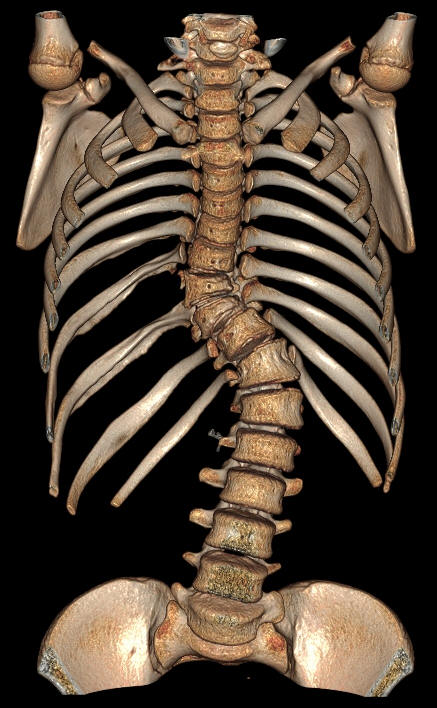

CT检查成像原理与DR类似,使用的是X射线,之后通过计算机成像。相较DR,CT可以多角度、多层面、多功能扫描成像,就像把一个面包切成多个平面进行观察。

而CT检查是把面包切片来看,获得的是真正的断面图像,没有层面以外的结构干扰。虽然细节看的更清楚了,但它就不是一块完整的面包了。

CT开展项目:适用于颅脑、眼眶、颞骨、副鼻窦、颅骨、颈部、胸部、心脏、腹部、盆腔、脊柱、椎间盘、四肢骨关节等部位的检查。能进行全身各部位常规、增强扫描及三维重建、体层高清成像,满足全身各系统组织器官的影像学检查要求。